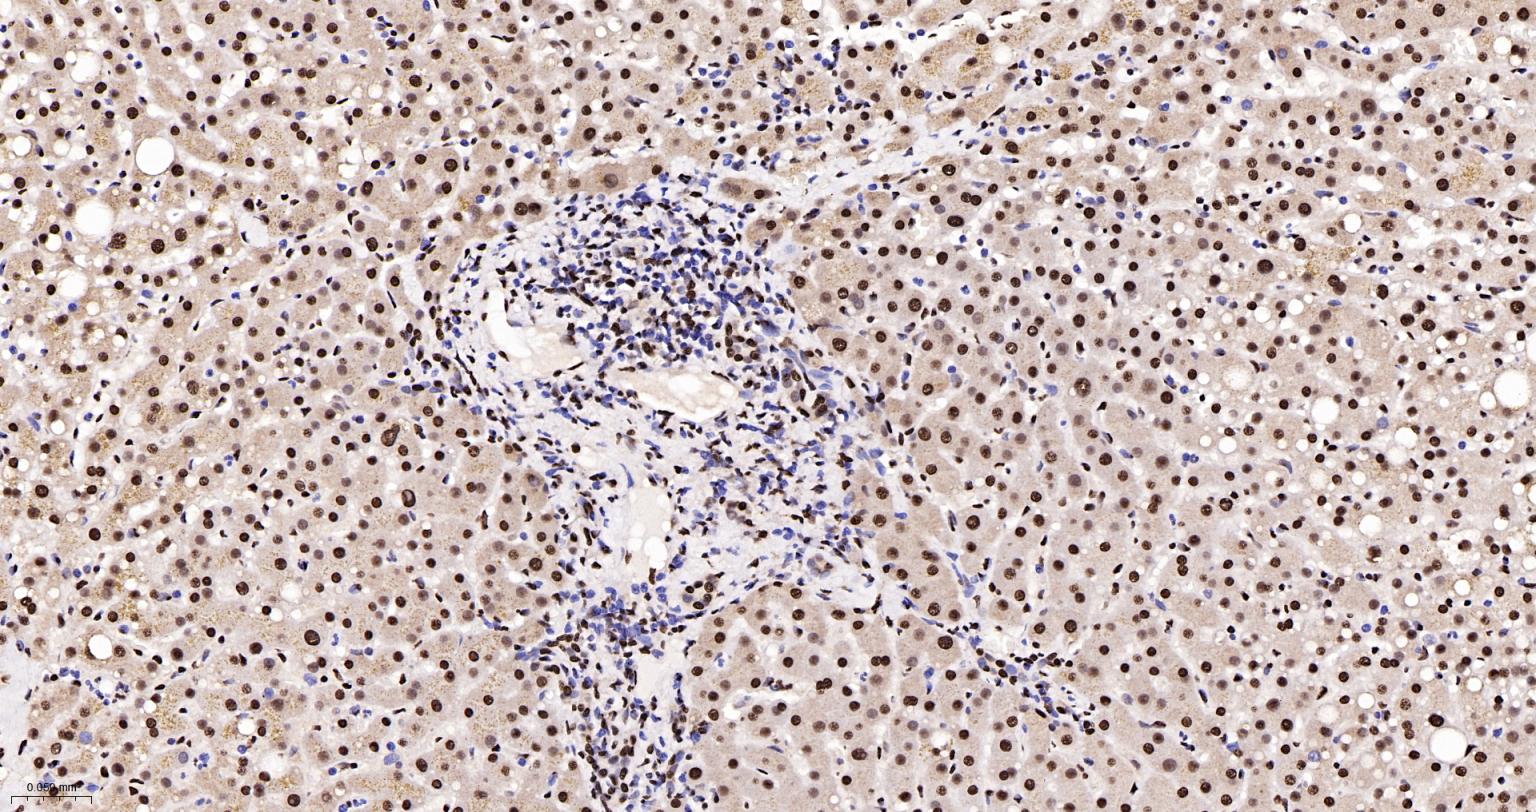

Paraformaldehyde-fixed, paraffin embedded Human Liver; Antigen retrieval by boiling in sodium citrate buffer (pH6.0) for 15 min; The section was incubated with hnRNP K Monoclonal Antibody, Unconjugated (bsm-61246R) at 1:200 overnight at 4°C, followed by conjugation to the bs-0295G-HRP and DAB (C-0010) staining.